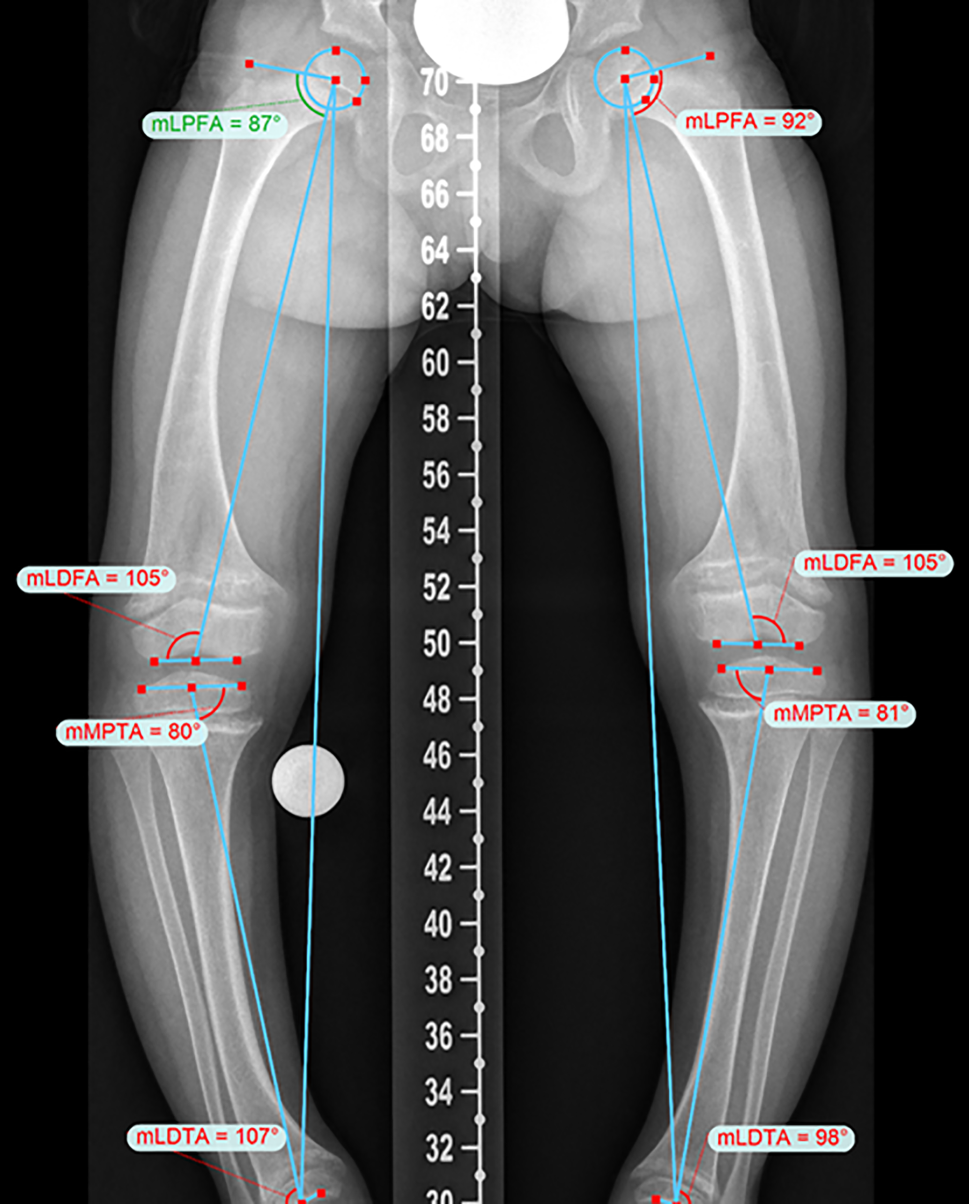

Surgical treatment plans need individual, careful and comprehensive preoperative deformity analysis. Multiple angles on standing X‑rays have to be measured to choose the right surgical technique and the accurate amount of correction (Fig. 2; [31, 32]). Different software programs such as Trauma CAD software (Voyant Healt, Petach-Tikva, Israel) or the Bone Ninja (Rubin Institute for Advanced Orthopedics, Sinai Hospital of Baltimore; Baltimore, MD, USA) app can help to analyse the deformity and make our treatment plans more understandable for our patients.

Fig. 2

Accurate preoperative deformity analysis allows an optimizes surgical treatment approach in patients with X‑linked hypophosphatemic rickets